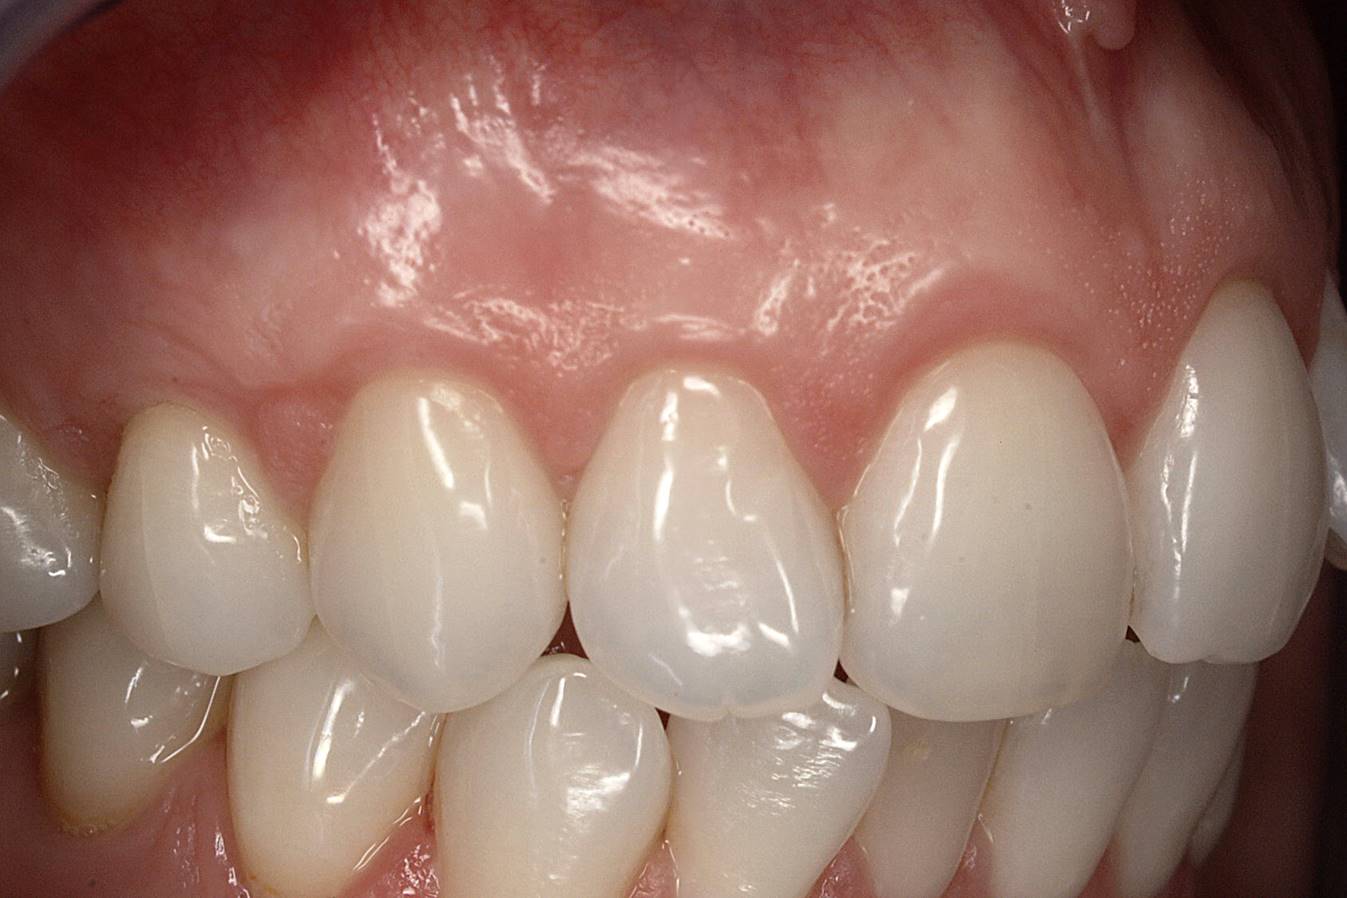

A male patient in his 30s presented for treatment of increasing recession he had had over his lifetime. Upon examination, a complete lack of gingiva on the facial of tooth No. 6 was observed. Although he had about 1.5 mm of gingiva on the facial of tooth No. 7 (Figure 4), both teeth probed to 3 mm. This indicated an absence of attached gingiva on the facial of these teeth in addition to increasing recession.

With a low lip line, the patient was not concerned about esthetics, and he was not experiencing root sensitivity. It was determined and agreed that a FGG was the best option for him in order to increase the amount of gingiva and limit further recession.